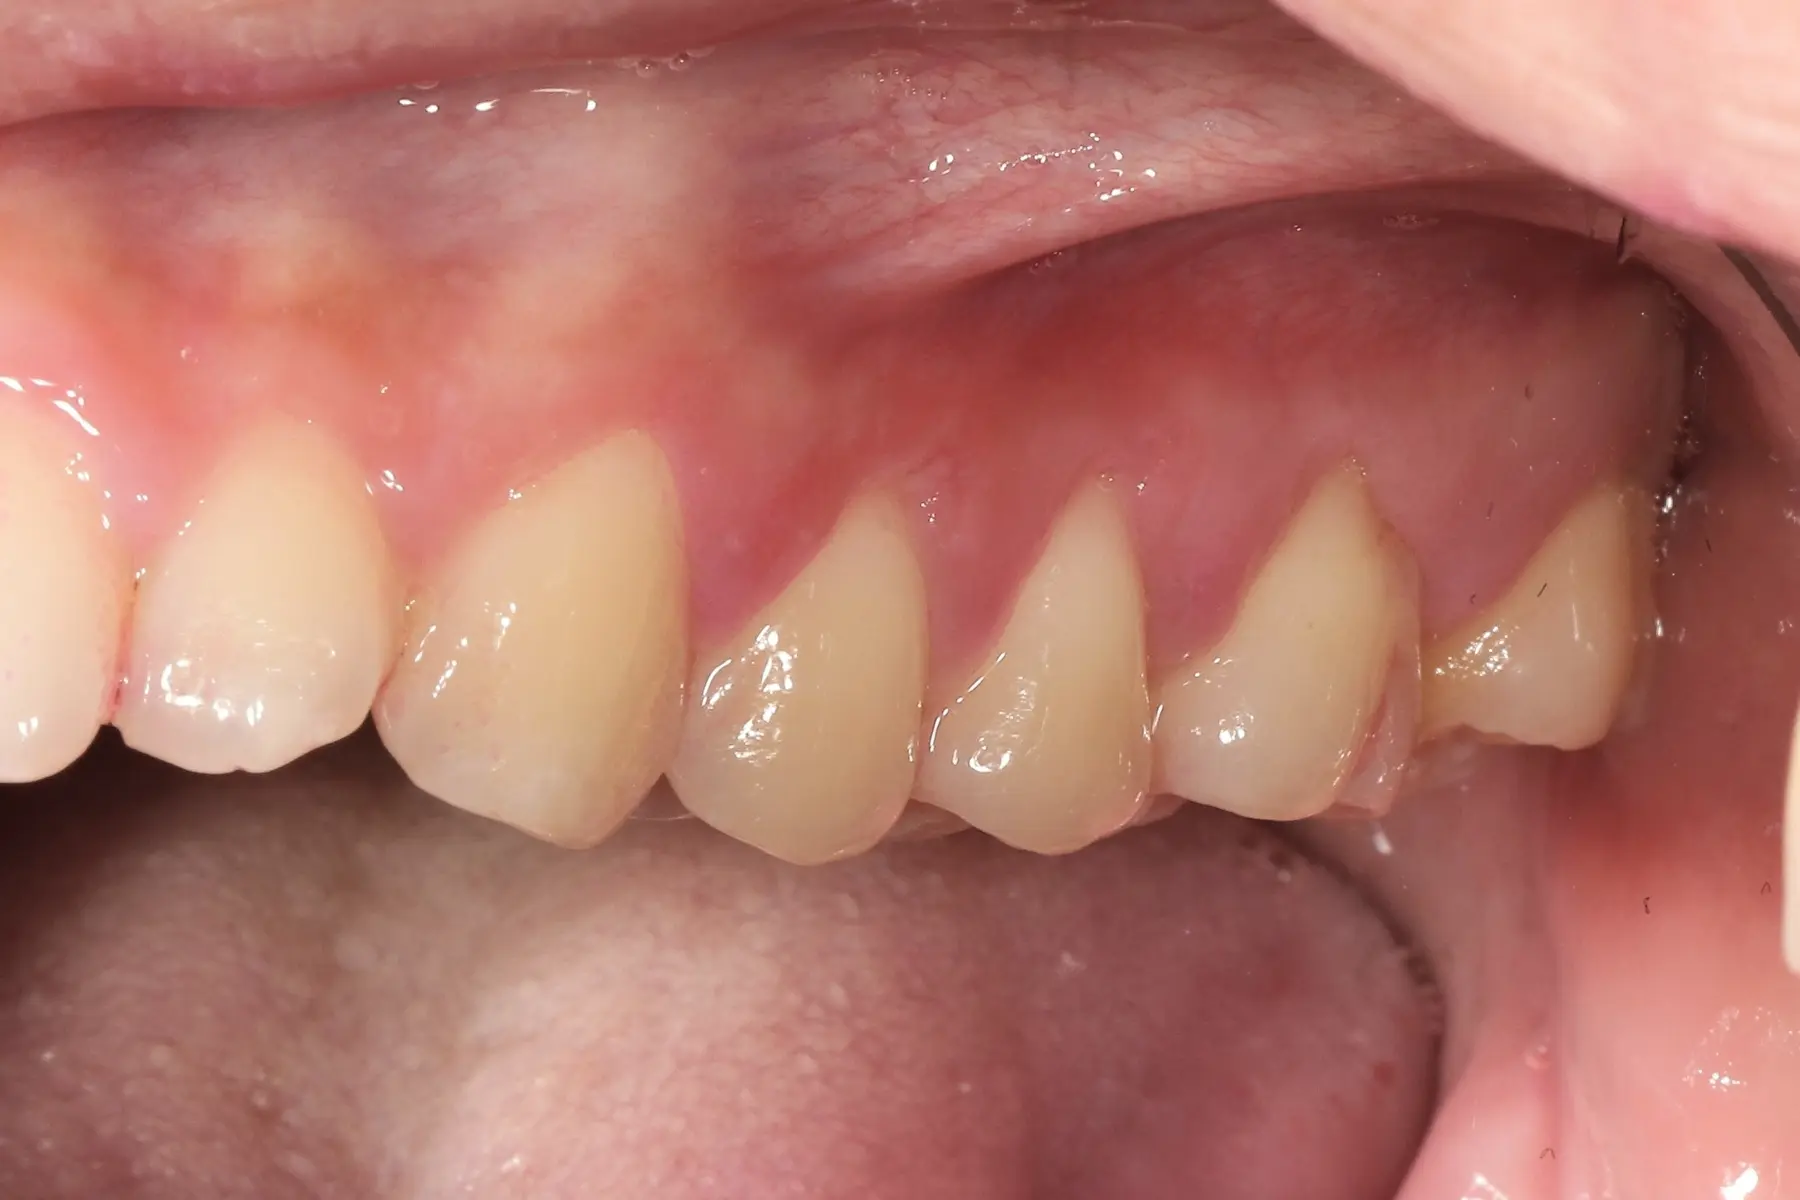

• 術前 43

術後 41

仿生美學樹脂

主治醫師

• 陳暐文

治療時間

單次療程

主訴

矯正完成下排前牙出現黑三角